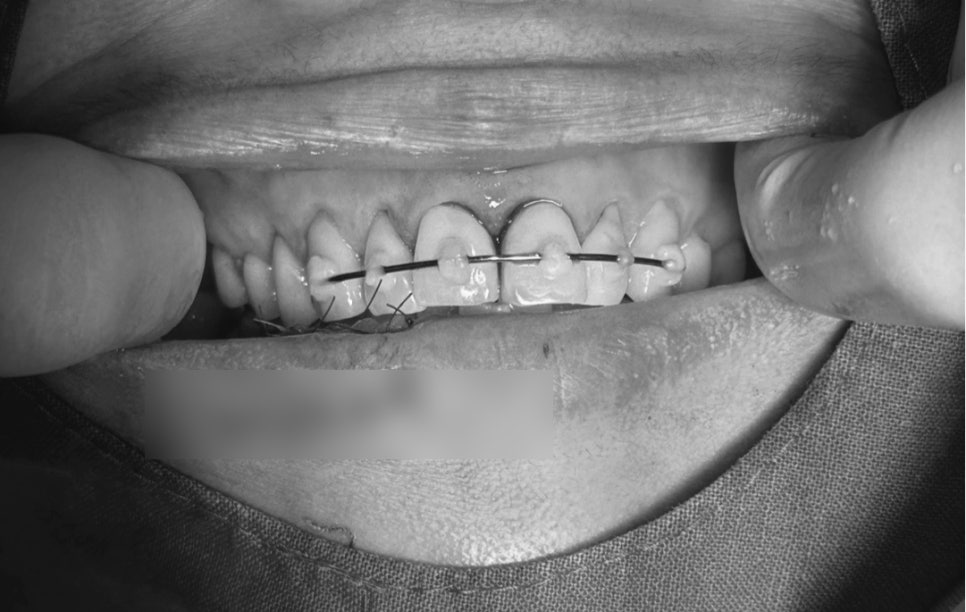

Alveolar bone fracture and front tooth stabilization device

- Alveolar bone fracture & front tooth stabilization

When a front tooth is pushed backward or becomes loose due to impact,

it must be returned to its proper position and stabilized for a certain period.

In this case as well,

were performed.

This helps the tooth reattach stably to the bone.

If it is not stabilized or if treatment is delayed, the tooth may move further and the risk of nerve necrosis increases.